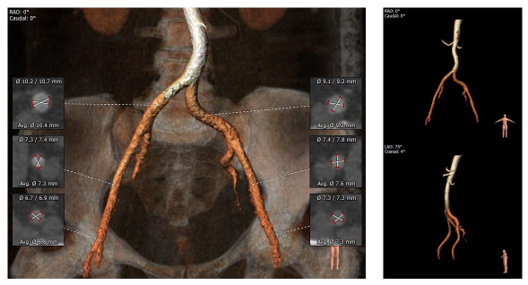

入路测量:

股动脉入路可